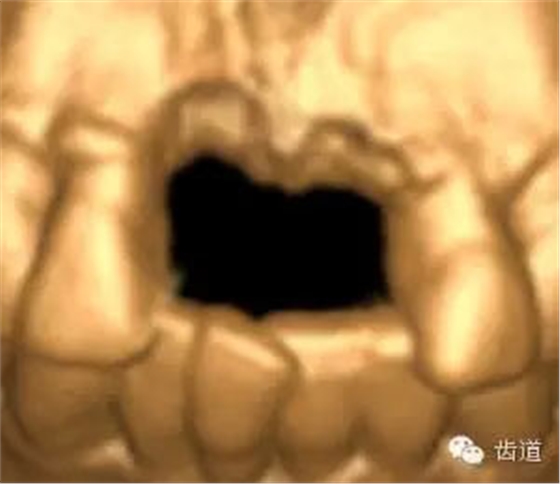

Cbct重建

治療方案:

患者對(duì)美觀要求較高,與患者溝通后,擬定采用骨環(huán)技術(shù),同期種植并增加骨寬度和高度。

患者不愿才用自體骨移植,遂建議采用同種異體骨骨塊(皮質(zhì)骨)進(jìn)行骨環(huán)手術(shù)。 種植手術(shù):